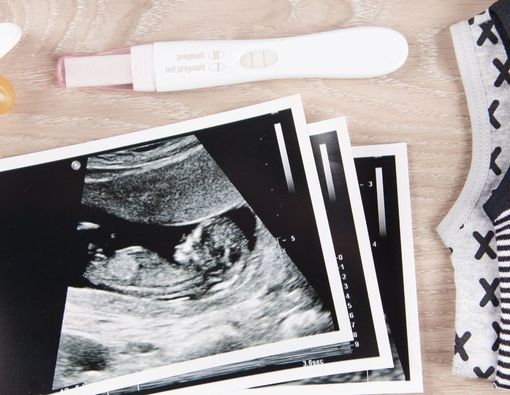

Dalam pemeriksaan USG minggu ke-12, beberapa perkembangan janin berikut ini dapat terlihat:

Pada pemeriksaan USG, ibu hamil akan melihat bentuk bayi yang sudah tumbuh seperti manusia. Tangan, kaki, dan jari sudah terbentuk. Wajah bayi juga sudah mulai terlihat walaupun belum sempurna karena lemak di pipi masih dalam proses pembentukan.